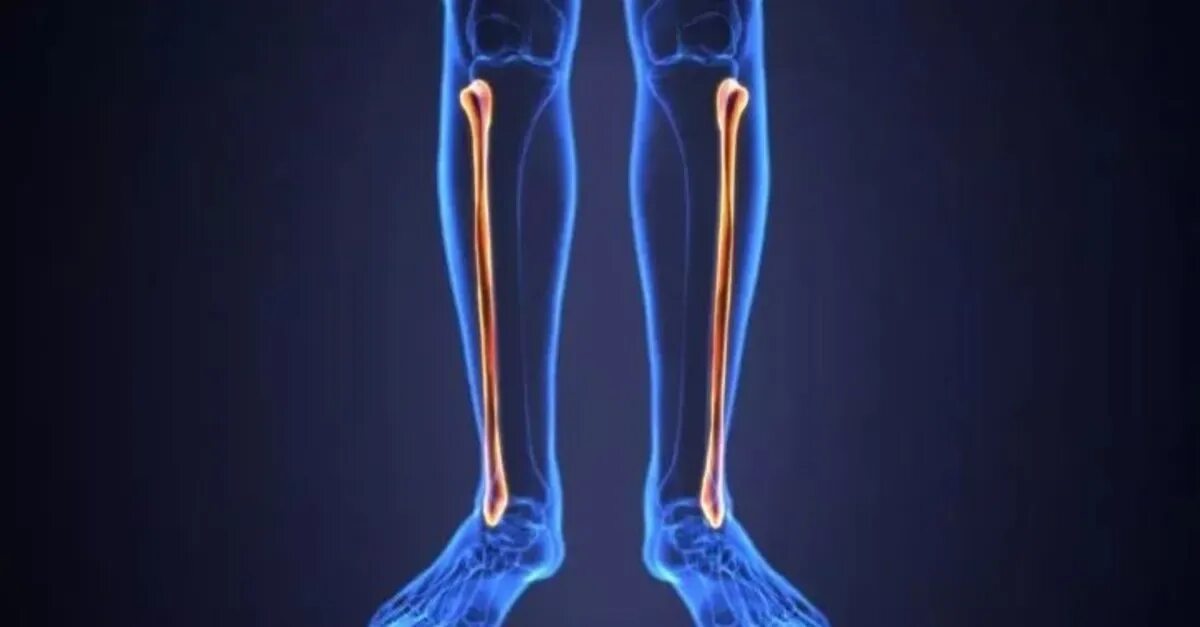

Curved tibia fibula